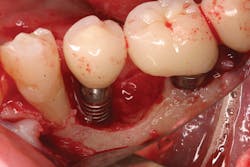

Once again, the literature is replete with case reports and case series describing soft- and hard-tissue loss due to excess dental cement left at the time of implant crown insertion.8 In one study, 90% of the implant crowns inserted with cement exhibiting inflammation and bleeding upon probing were due to cement in the peri-implant sulcus.9 Cement acts as a nidus for bacteria and induces a rapid hard-tissue loss around the dental implant fixture (figures 2 and 3).

Detecting excess cement can usually be done with a radiograph if the cement is located in the interproximal region and is radiopaque (figure 4).